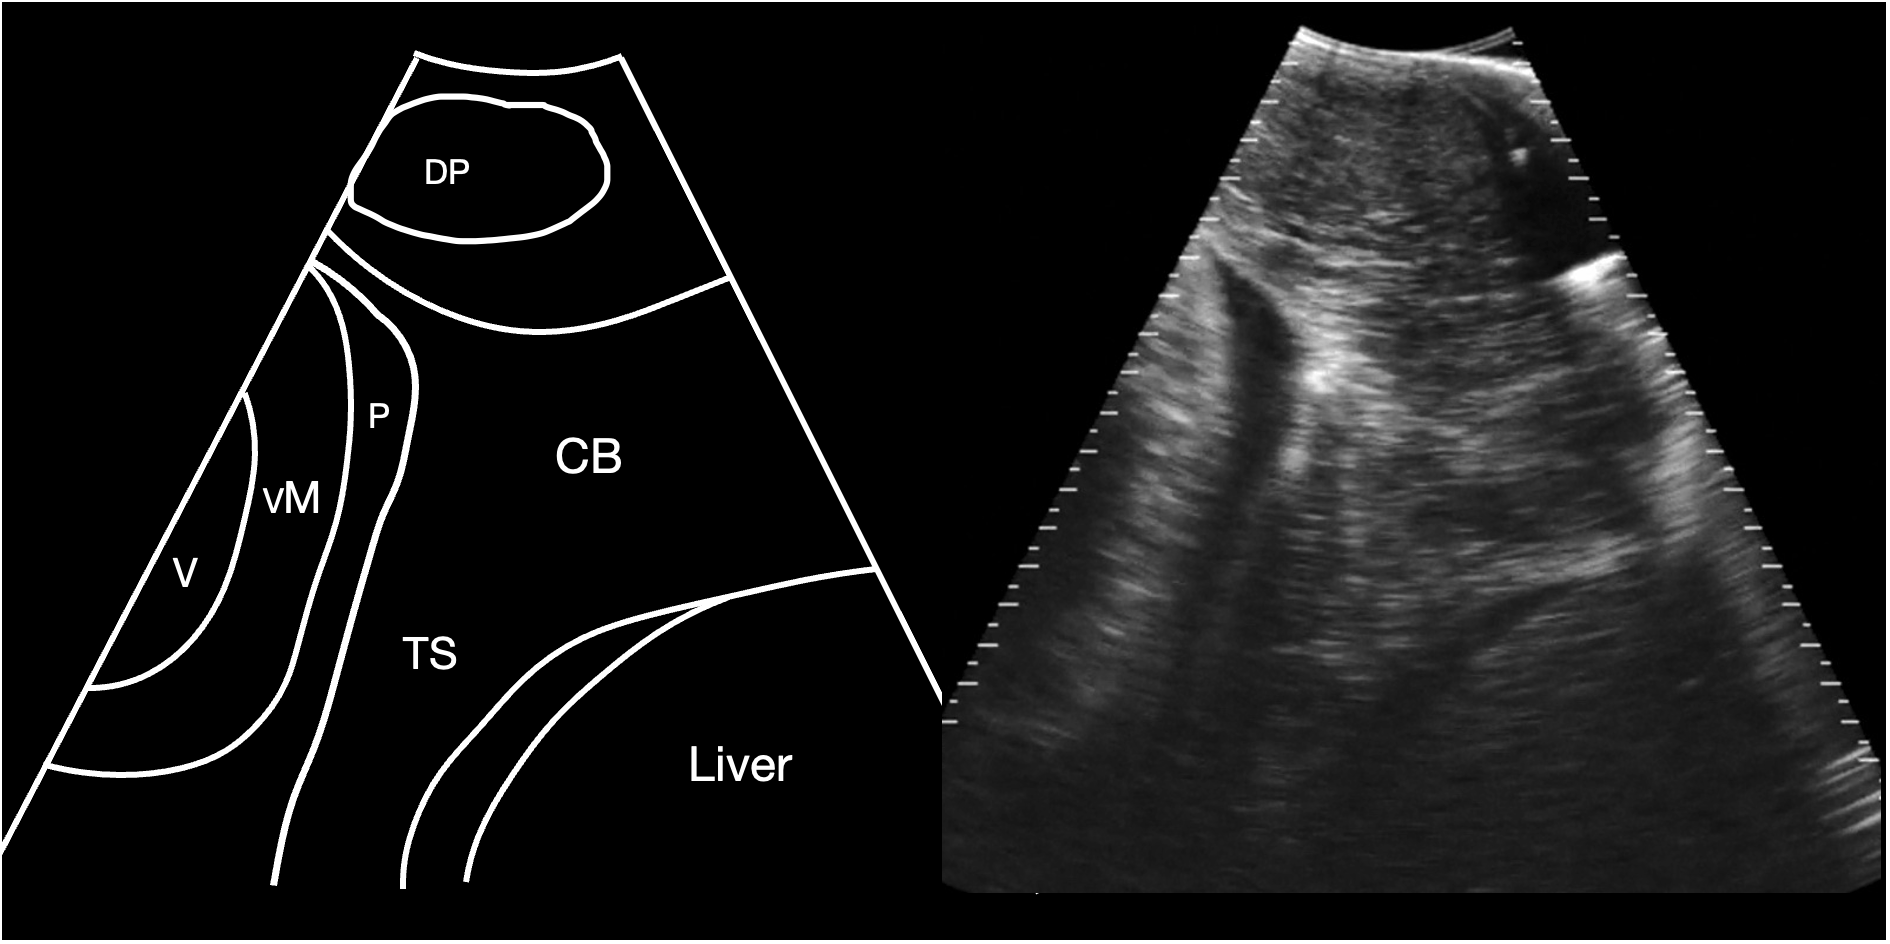

Figure 2

Schematic diagram (left) and corresponding sagittal sonogram (right) acquired at the pectoral line, showing the transverse septum. CB Coracoid bar; P Pericardial fluid; TS Transverse septum; VM ventricular myocardium; V Ventricular lumen. See Supplementary Video S1.

The cranial margin of the midline crease and the pectoral line were used as landmarks to commence sonographic evaluation of the sharks, and at this level the cranial extent of the abdominal cavity was identified, bounded by the transverse septum, identified as a broad shelf of moderately echoic tissue that separated the abdominal cavity caudally from the pericardial space cranially (Figure 2). The base of this septum was confluent with the coracoid bar, identified as a broadening of the ventral septum in the body wall. Also identified at this level was the depressor pectoralis muscle, imaged in transverse and forming an ovoid hypoechoic structure in the hypaxial musculature.